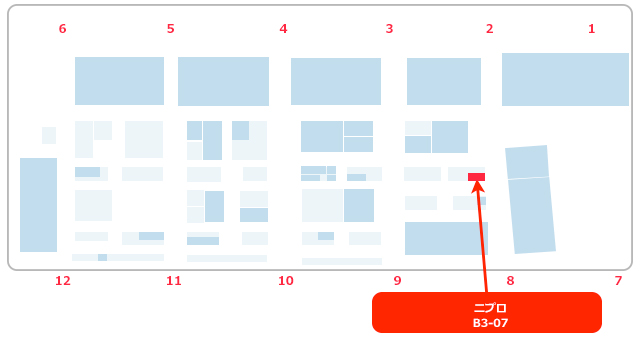

ブースNo.B3-07

●ニプロブース